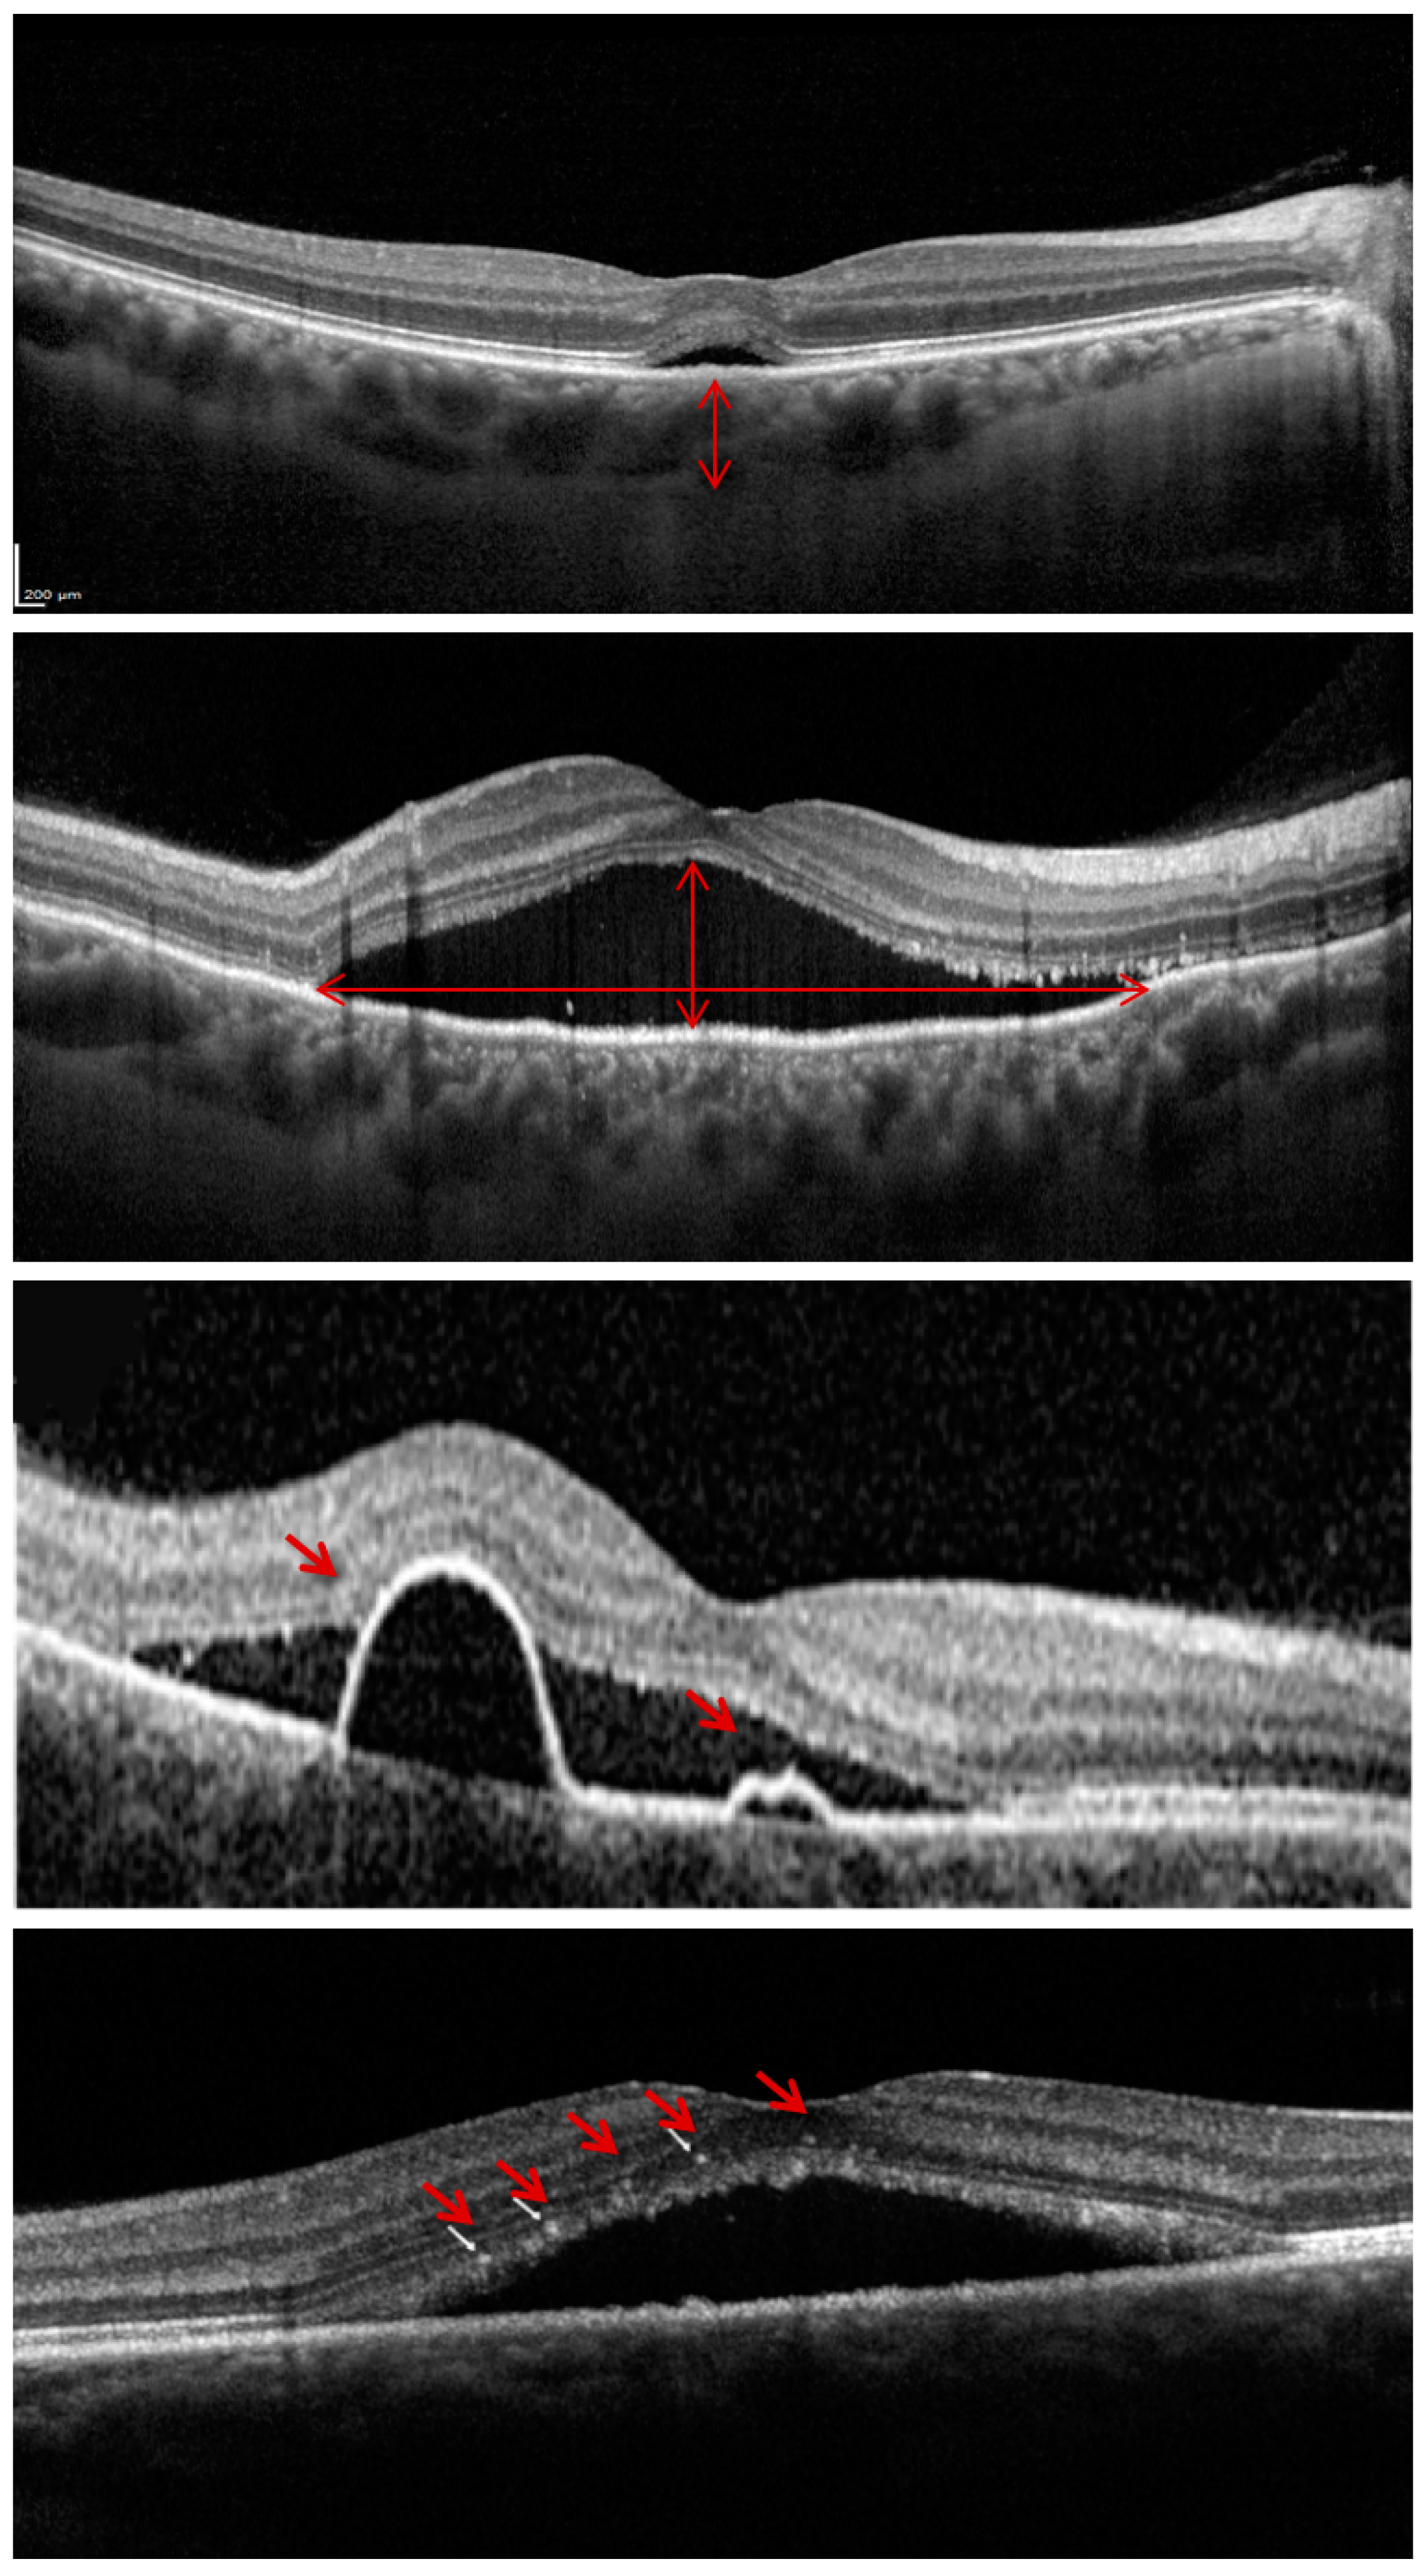

2.3. OCT Analysis